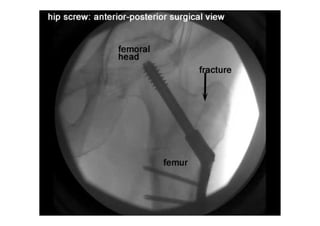

RADIOLOGIA DO

TRAUMA DO ESQUELETO

Referência: http://www.accessexcellence.org/RC/VL/